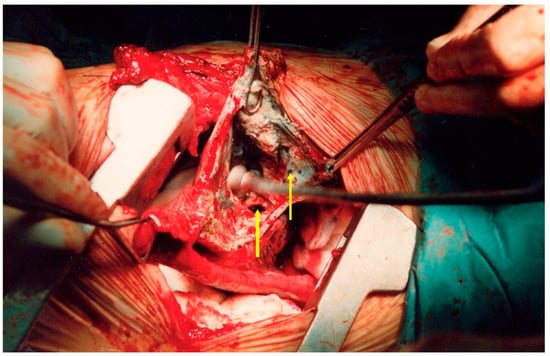

These were addressed synchronously with bilateral posterior thoracotomies in a prone position, using our experience in bilateral lung transplantation with this approach (left side: through the VII left intercostal space; right side: through the VI right intercostal space). Gentle manual palpation is necessary for localization. Wedge-type excisions were performed using standard automatic endostaplers of 45/60 mm length on clear macroscopic margins of minimum 1 cm interval (Figure 3). Histopathological confirmed extensive tissue necrosis and echinococcal structures (Figure 4). The parasite lesions may extend directly across the diaphragm and their rupture is a respiratory emergency.

Figure 4. Histopathological specimen of case 1. Multiple cystic cuticular structures surrounded by abundant necrotic tissue and inflammatory reaction. Other areas showed in addition granulation tissue and fibrosis (H&E staining, 100×).